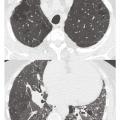

L’hypertension pulmonaire (HTP) associée aux maladies respiratoires chroniques est fréquente chez les patients présentant une bronchopneumopathie chronique obstructive (BPCO) avec ou sans emphysème, une pneumopathie interstitielle diffuse (PID), un syndrome emphysème-fibrose ou encore une hypoventilation alvéolaire. Ces HTP…